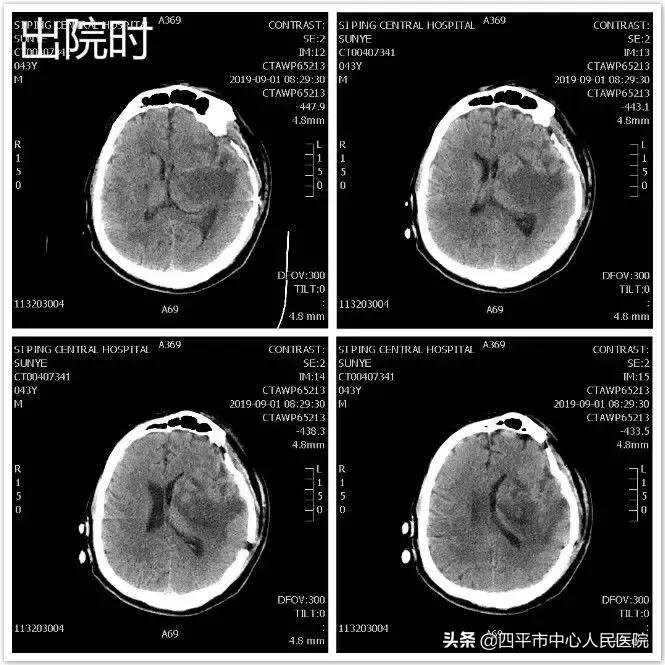

Case 5 左侧脑出血,发现左侧后交通动脉未破裂动脉瘤

患者孙XX,入院前约21小时无明显诱因突发言语不清伴右侧肢体活动不灵,表现为肢体瘫痪,既往高血压病史约10年,最高可达180mmHg,不规律服用降压药物急被家属送至我院就诊,急送我院急诊给予查头部CT后,示脑出血。患者入院后病情呈进行性加重,患者符合手术指征,行头部CT定位见出血量增加,头部CTA示相当于左侧后交通动脉起始部小动脉瘤,李晓东主任带领马龙医生在清除脑出血的同时将动脉瘤夹闭,出院时,患者病情平稳,预后较好。